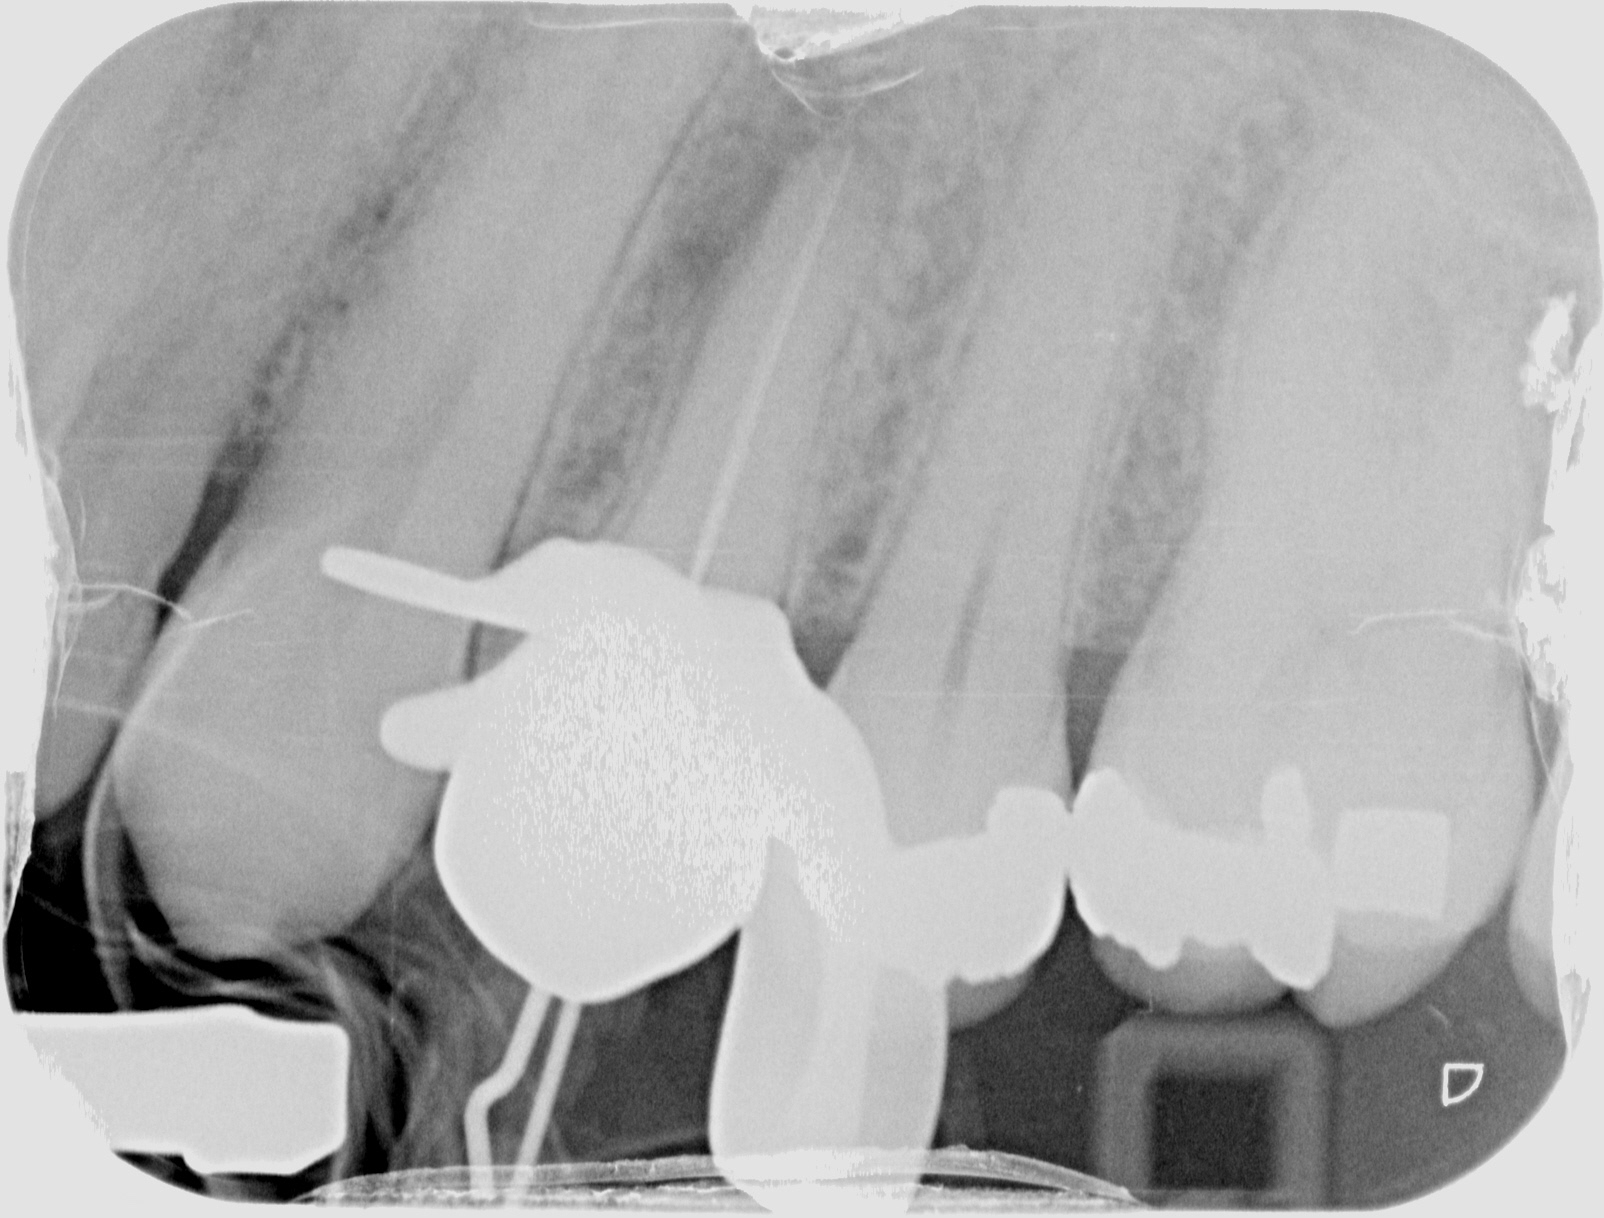

SUCCESSFUL 14

INITIAL

WORKING LENGTH

FINAL

3 MONTHS FOLLOW UP